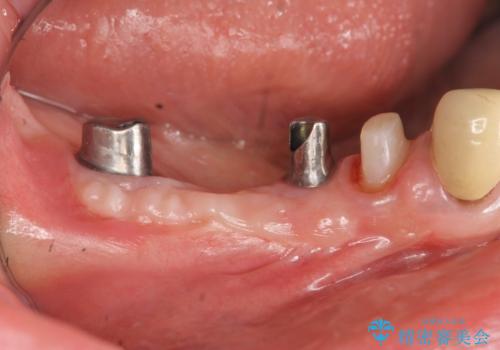

狭小な歯槽骨に対するインプラント治療

- 歯を失い噛めないこと、骨の幅が狭く他院でインプラント治療が難しいと断られ、当院でのインプラント治療が可能かどうか相談来院されました。

骨の造成、角化歯肉の移植を行いインプラント周囲の環境を整えた治療を計画します。